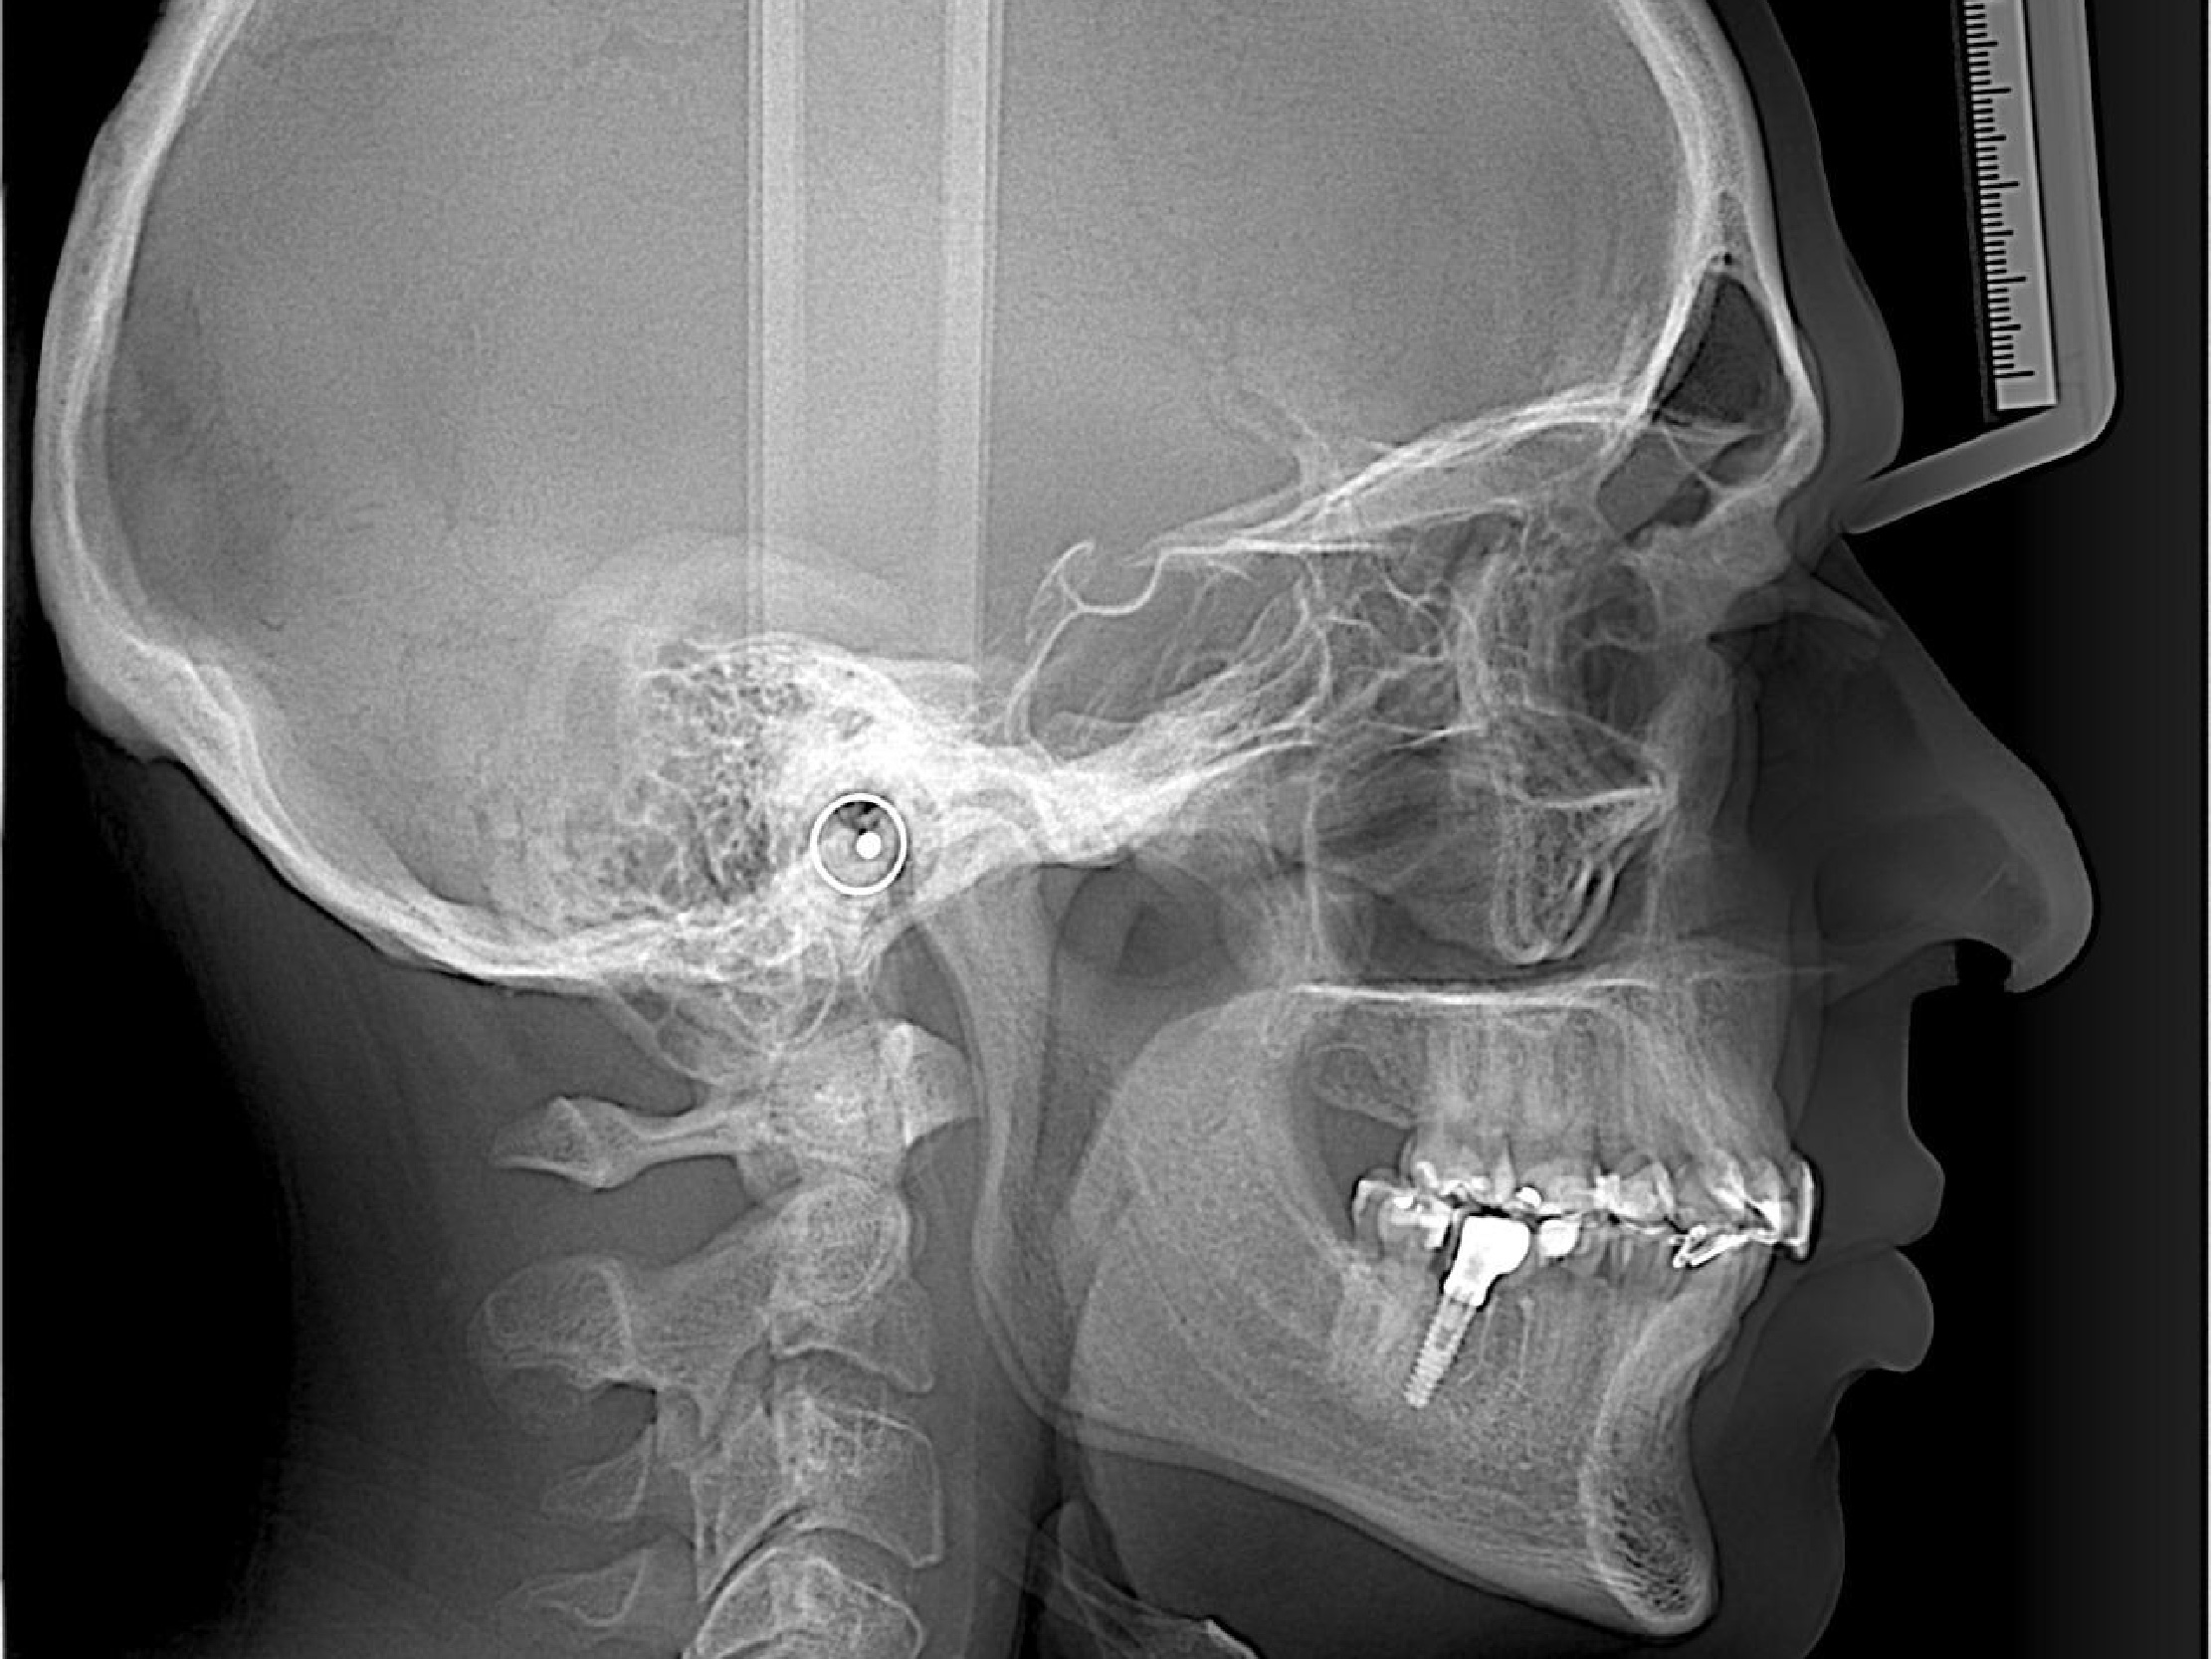

Disparo Ceph